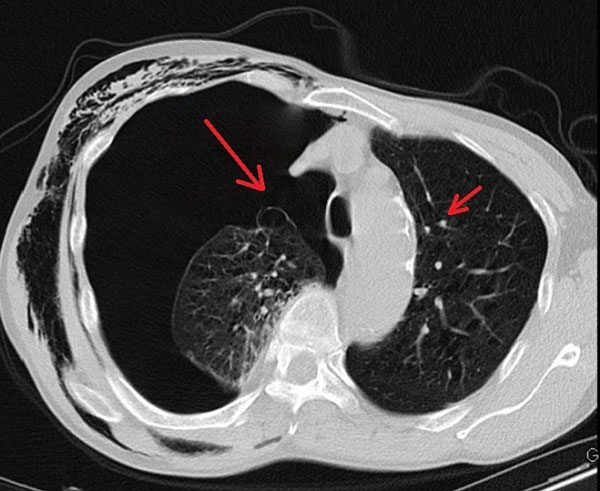

Ngày 19/12, VietNamNet dẫn lời bác sĩ Nguyễn Văn Lâm, Khoa Ngoại tổng hợp, Bệnh viện Đa khoa Đức Giang (Hà Nội), cho hay Bệnh nhân là ông N.V.K, 67 tuổi ở Gia Lâm, Hà Nội, có tiền sử nghiện thuốc lá, thuốc lào 40 năm nay.

Ông vào viện trong tình trạng đau ngực bên phải, khó thở nhiều. Kết quả chụp X-quang tim phổi cho thấy bị tràn khí màng phổi phải nhiều, được đặt dẫn lưu khí bằng catheter.

Sau hai ngày điều trị tại khoa Ngoại tổng hợp, tình trạng của ông K. không cải thiện, các bác sĩ chỉ định chụp CT ngực, phát hiện có nhiều kén khí rải rác ở hai bên đỉnh phổi và đáy phổi phải.

Các bác sĩ nhận định đây là trường hợp tràn khí màng phổi do vỡ kén khí, cần phẫu thuật nội soi. Điều này giúp bệnh nhân cải thiện chức năng hô hấp, vận động; tránh các nguy cơ khó thở kéo dài, tràn dịch màng phổi, áp-xe phổi, viêm mủ màng phổi.

Sau 3 ngày nội soi cắt toàn bộ các kén khí và khâu phục hồi lại nhu mô phổi, bệnh nhân ổn định, phục hồi tốt, phổi giãn nở tốt, có thể vận động nhẹ nhàng, đi lại bình thường.

Trao đổi với Dân Trí, BS Lâm cho biết thêm: "Kén khí ở phổi là tình trạng đặc trưng bởi sự căng giãn thường xuyên của đường dẫn khí từ tiểu phế quản tận cùng trở xuống, kèm theo có sự phá hủy vách các phế nang không phục hồi.

Kén khí phổi xảy ra cục bộ tại vùng của phổi, có thể một hoặc nhiều kén tập trung ở thùy trên nhiều hơn thùy dưới, thường kết hợp với viêm phế quản mãn tính, giãn phế nang khu trú, lao, hoặc bội nhiễm gây áp xe phổi…".

Bệnh làm tăng khoảng chết sinh lý và gây chèn ép tổ chức phổi lành xung quanh. Nếu không phát hiện, phẫu thuật kịp thời sẽ gây xẹp cả phổi ở bên mọc kén, đẩy trung thất ép cả phổi bên đối diện, đưa đến hậu quả là suy hô hấp rất nặng nề. Thậm chí nếu tăng áp lực trong đường thở bệnh nhân, kén khí có thể vỡ gây tràn khí màng phổi dẫn tử vong.

BS Lâm khuyến cáo, đối với những bệnh nhân có những yếu tố nguy cơ do hút thuốc lá thuốc lào nhiều năm hoặc bệnh phổi nên đi khám định kì, để phát hiện các bệnh lý liên quan về kén khí nói riêng và bệnh phổi nói chung, từ đó có hướng điều trị kịp thời.